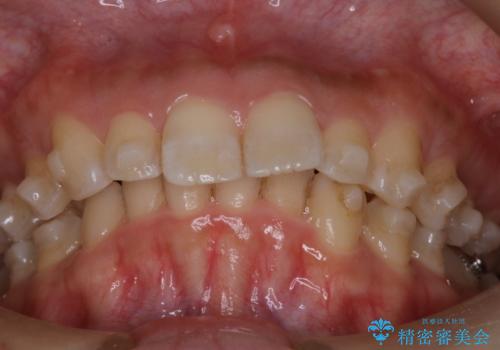

- 上の前歯の出っ歯と前歯の深い咬み合わせを治したいとのことで来院された患者様です。

上顎の歯は後方移動とIPR(歯と歯の間を削る)によって口元が引っ込むように、下顎は歯列全体の拡大とIPRによって上顎とバランスよく咬み合うように設計し、インビザラインにより治療を行うこととしました。

上顎歯列の後方への移動量が多く、右側の奥歯の咬み合わせを改善する必要もあったため、治療には長期間を要しました。